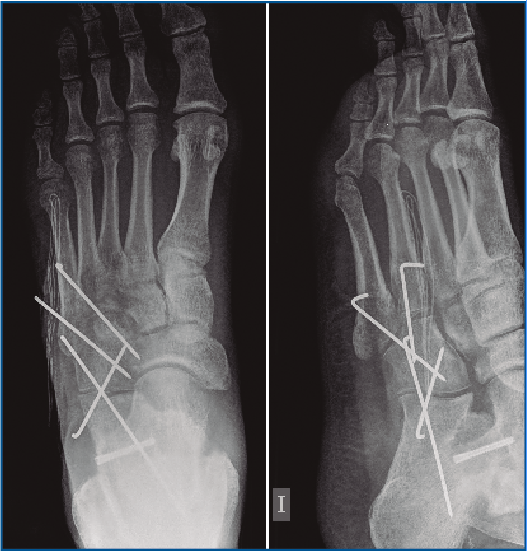

En la exploración destaca una inflamación y dolor en el borde externo del pie que no impide la deambulación. En la revisión de las pruebas complementarias (radiografía simple y TC) se confirman las lesiones previamente diagnosticadas, junto con una luxación del cuboides plantomedial (Figuras 1 y 2).

Figura 1. Radiografía prequirúrgica a la semana de evolución del traumatismo. Obsérvese el desplazamiento medial del cuboides.

Es intervenido a la semana de la lesión realizándose, bajo anestesia raquídea e isquemia del miembro, una incisión dorsolateral desde la articulación calcaneocuboidea hasta la base del 4.º MTT. Se expuso el cuboides reflejando el extensor corto a dorsal y peroneo corto a plantar y se evidenció la desalineación del cuboides con el 4.º y 5.º MTT y el calcáneo creada por la luxación. Se realizó una reducción manual del mismo y una fijación con 2 agujas de Kirschner (agujas K) metatarsocuboideas, 1 aguja cuboideocalcánea y 1 calcaneocuboidea, realizándose al mismo tiempo una fijación de la apófisis lateral del astrágalo con un tornillo canulado (Figuras 3, 4 y 5). Se mantuvo 6 semanas inmovilizado, momento en el que se retiraron las agujas K. A la 6.ª semana, se inicia la carga con ortesis de carga hasta la 8.ª semana.

Figura 5. Imagen intraoperatoria de la reducción del cuboides y fijación con 2 agujas de Kirschner metatarsocuboideas, 1 aguja cuboideocalcanea y 1 calcaneocuboidea.

La evolución clínica y radiológica ha sido satisfactoria, permitiendo un aumento progresivo de las actividades (Figuras 6 y 7). A los 2 años de seguimiento el paciente no refiere limitaciones, con una puntuación en la escala de la American Orthopaedic Foot and Ankle Society (AOFAS) de 90.

Figura 6. Radiografía al mes de la cirugía con la correcta reducción ósea.